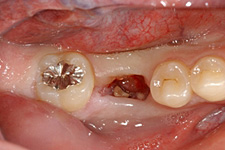

移植中の様子

第一大臼歯の抜歯後2週間で移植を行いました。

移植のために抜歯された右下の親知らず。歯根がまだ完成していない若い歯です。

移植後

移植直後の歯の様子。